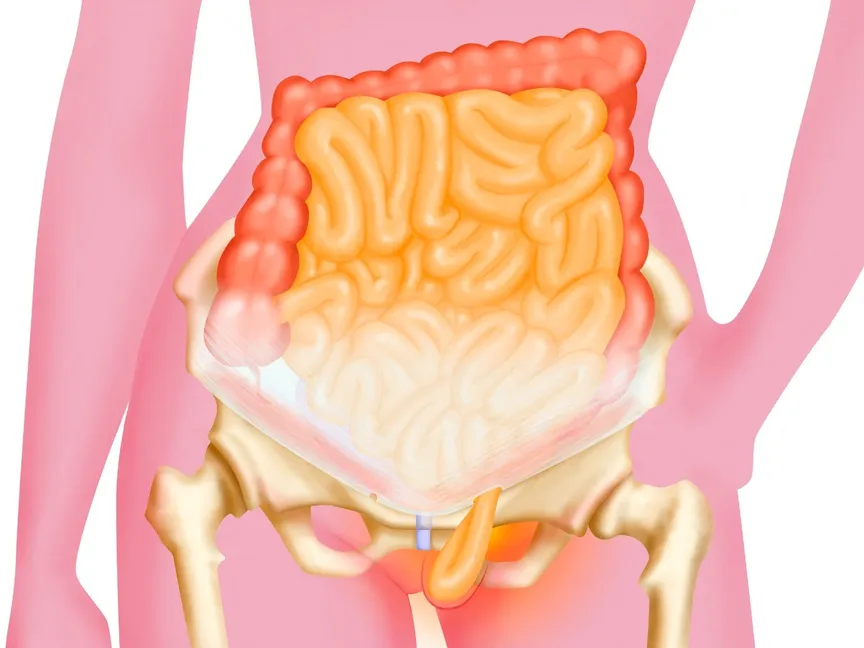

يحدث الفتق الحجابي عندما يبرز الجزء العلوي من المعدة عابراً من العضلة الكبيرة التي تفصل البطن عن الصدر، وهي العضلة المسماة بالحجاب الحاجز.

توجد في الحجاب الحاجز فتحة صغيرة تسمى الفُرجة الحِجابية. ويمر الأنبوب الذي تبتلع به الطعام -الذي يُطلَق عليه المريء- عبر الفُرجة الحِجابية قبل أن يتصل بالمعدة. وفي الإصابة بالفتق الحجابي، تبرز المعدة من خلال تلك الفتحة باتجاه الصدر.

يحدث الفتق الحجابي عندما يسبب ضعف أنسجة العضلات بروز المعدة للأعلى من خلال الحجاب الحاجز. والسبب وراء حدوث هذا لا يكون واضحاً دائماً. لكن قد يكون الفتق الحجابي ناتجاً عما يلي:

- الضغط المستمر والشديد على العضلات المحيطة. يمكن أن يحدث ذلك أثناء السعال أو القيء أو الإجهاد أثناء التبرز أو ممارسة الرياضة أو رفع أشياء ثقيلة.